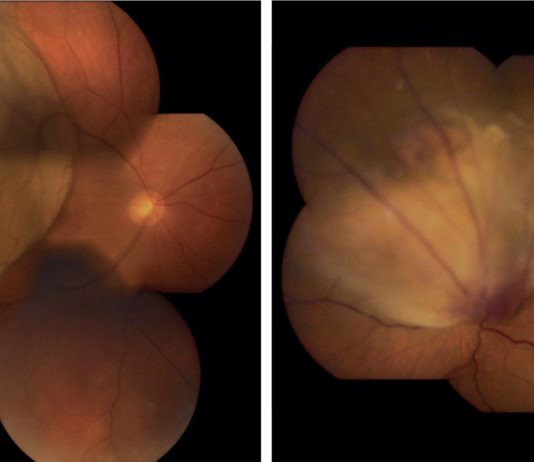

Neovascolarizzazioni maculari nell’atrofia geografica

La degenerazione maculare legata all’età (age related macular degeneration, AMD) rappresenta la prima causa di cecità nelle...